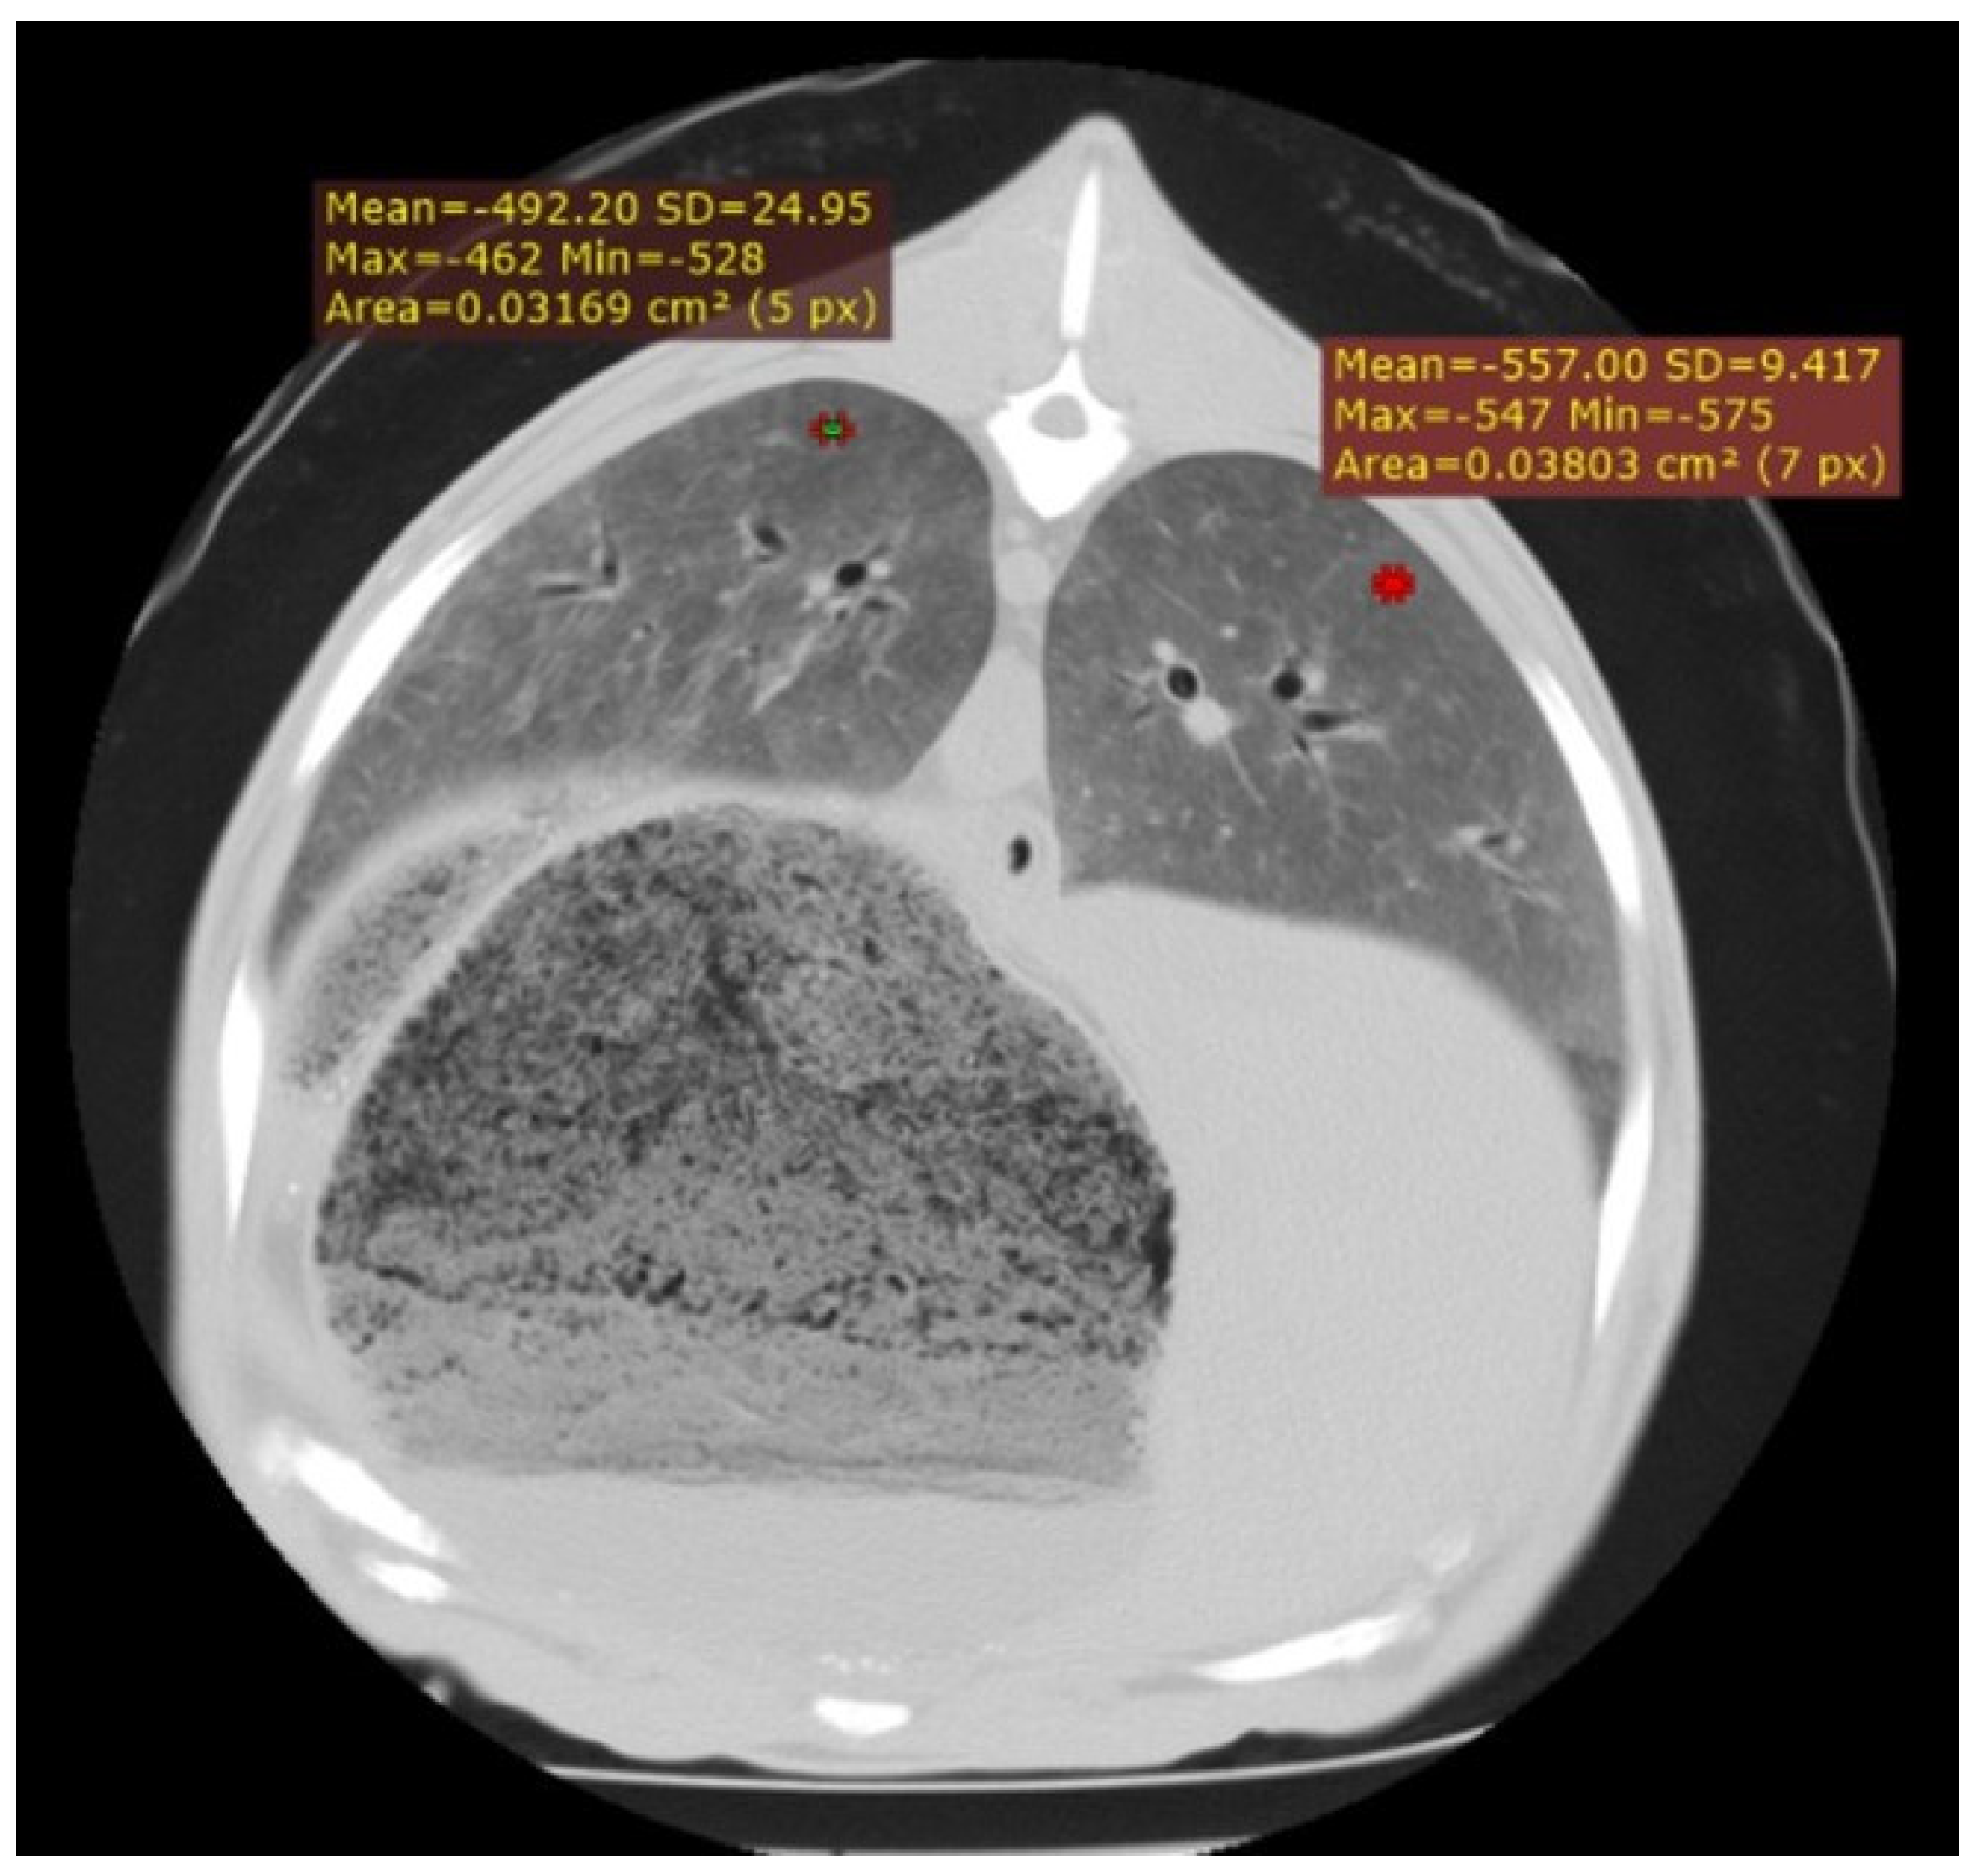

3.3.1. Interstitial Pneumonia (SRLV)

| SRLV | Diffuse, entire lung parenchyma | 800 to −400 HU | Severity-dependent: mild (−700 to −800 HU), moderate (−550 to −700 HU), severe (−400 to −550 HU); reflects cellular infiltration |